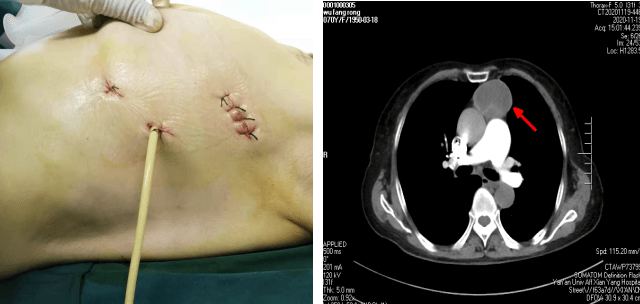

患者××,女,70歲,因“間斷腹部不適2月,加重10天” 于11月23日收入腫瘤/胸外科。胸部CT示前縱膈腫瘤。苗滿園主任帶領(lǐng)團(tuán)隊(duì)對該患者情況進(jìn)行了仔細(xì)的研究討論:縱膈腫瘤大小約10cm×6cm×6cm,邊界尚清,內(nèi)有鈣化,考慮良性腫瘤可能性大。與家屬溝通后選擇胸腔鏡下手術(shù)。手術(shù)團(tuán)隊(duì)經(jīng)精心術(shù)前準(zhǔn)備,于11月25日為患者實(shí)施全麻下“胸腔鏡下縱膈腫瘤切除術(shù)”。術(shù)中發(fā)現(xiàn)腫瘤起于心臟左前上方,經(jīng)主動脈弓前達(dá)胸腔頂。術(shù)中仔細(xì)分離,克服因心臟跳動及主動脈搏動的不穩(wěn)定性,保護(hù)好心臟、膈神經(jīng)、主動脈,出血量少,手術(shù)十分順利,歷時1小時,完整切除腫瘤。嚴(yán)格按圍手術(shù)期ERAS管道管理改進(jìn)措施,選用留置導(dǎo)尿管單根引流,避免傳統(tǒng)手術(shù)因引流管粗硬導(dǎo)致的術(shù)后疼痛不適,術(shù)后當(dāng)天即可獨(dú)立下床活動,生活完全自理?;颊呒凹覍俜浅M意,極大地提高了患者的就醫(yī)體驗(yàn)。